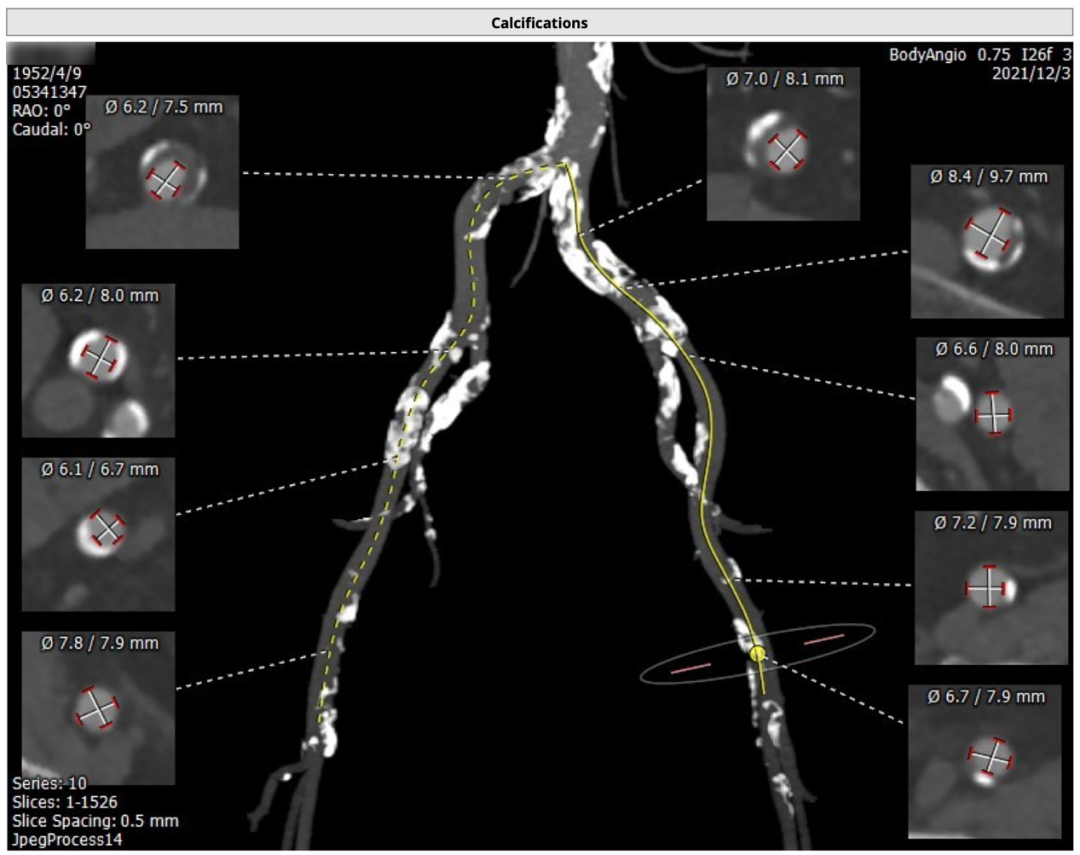

李妍主任提出该患者为TYPE 0型二叶瓣,重度钙化,主要分布于瓣叶交界,升主动脉较宽,窦部结构大,双侧股动脉入路均有钙化,术中注意轻柔操作,同时主动脉弓部大折角,大弯侧钙化侧瓣叶钙化重,可能存在输送系统过弓困难及跨瓣困难及瓣膜下滑风险术中密切注意,逐决定抓捕器辅助,24球囊预扩,选择植入VitaFlow Liberty ™30瓣膜,根据术中瓣膜形态及有无瓣周漏,做后扩准备。手术投照角度选取右窦最低,LAO结合CRA体位,保证看到窦底最底点,提高定位精度。

从右侧股动脉完成主动脉瓣根部造影,结果显示重度钙化,窦部结构大